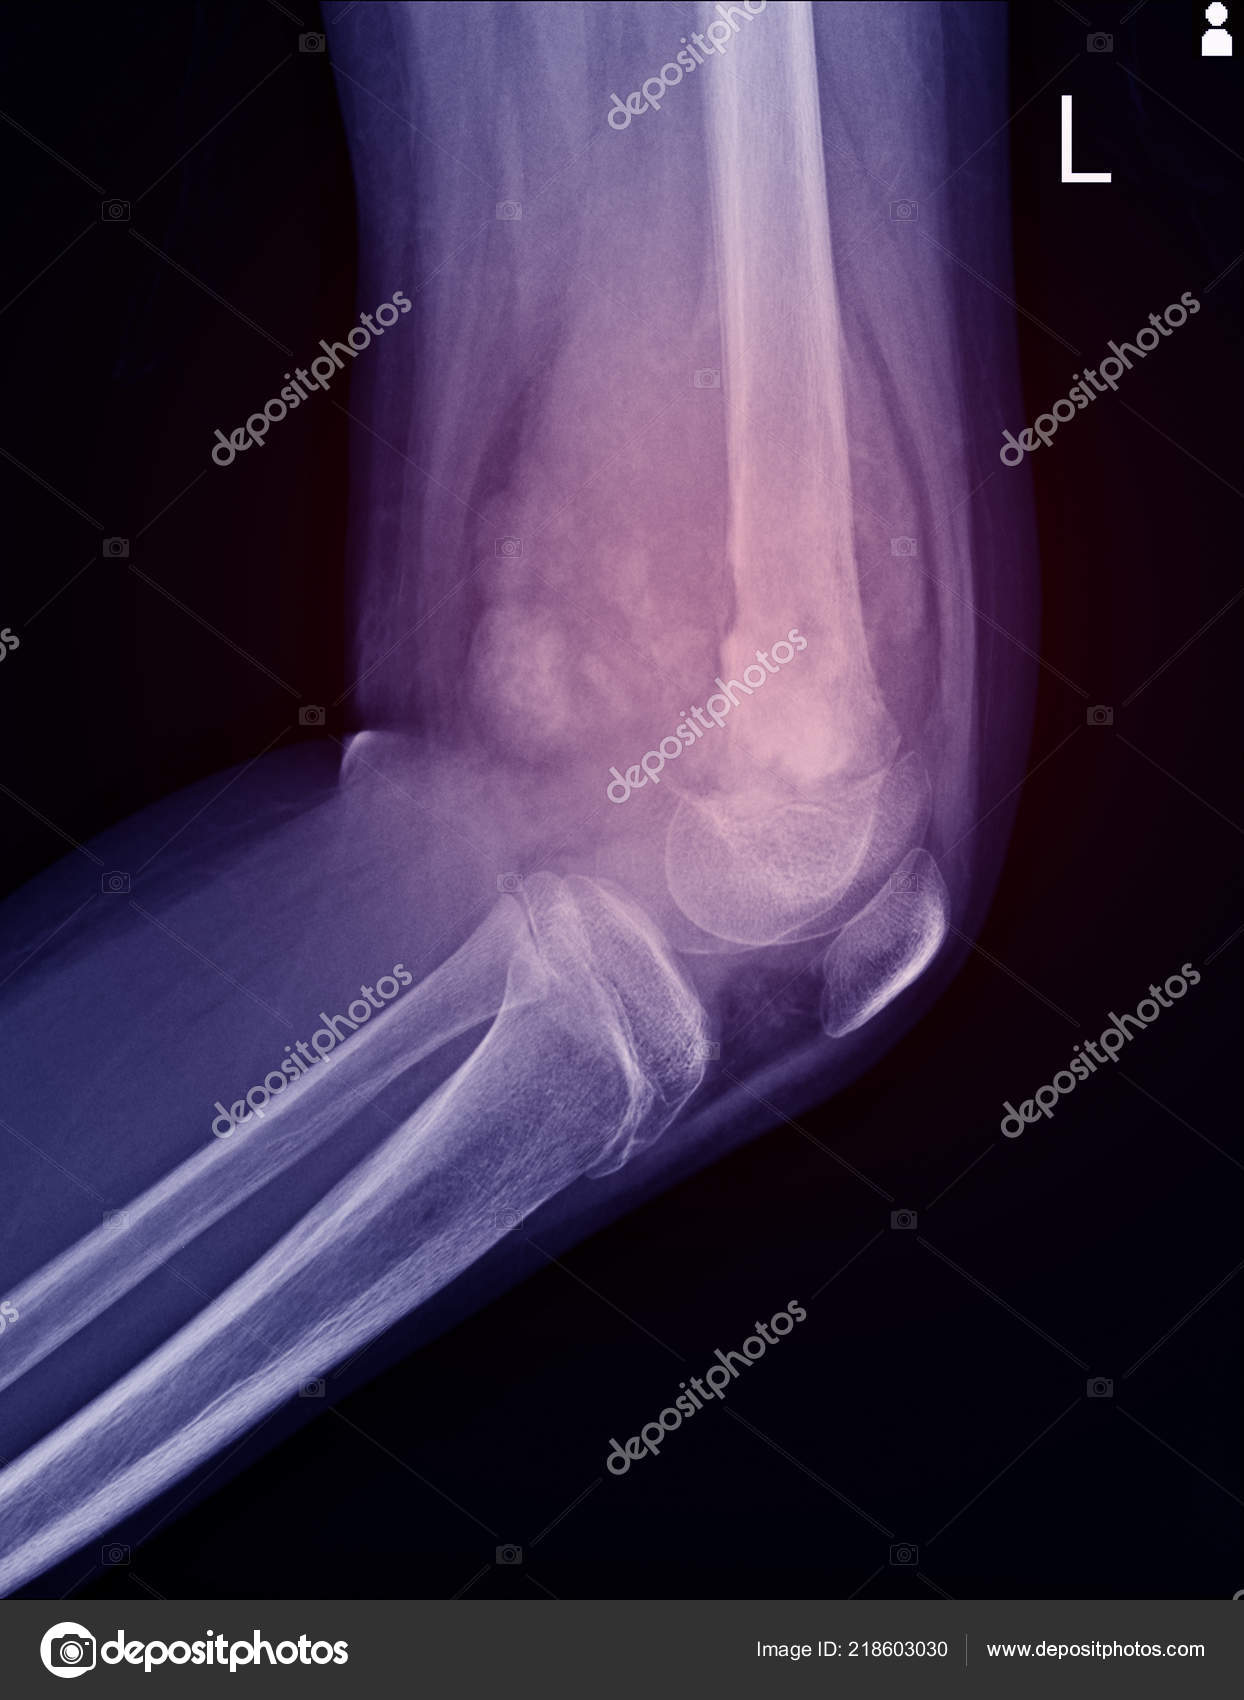

Scielo Brasil Knee Bone Tumors Findings On Conventional Radiology Knee Bone Tumors Findings On Conventional Radiology

Scielo Brasil Knee Bone Tumors Findings On Conventional Radiology Knee Bone Tumors Findings On Conventional Radiology from minio.scielo.br